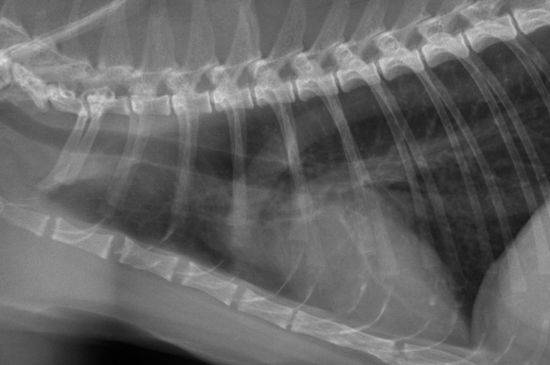

Les maladies pulmonaires chez le chien et le chat se traduisent généralement par une augmentation ou une diminution de l'opacité radiographique des poumons. Ces changements d’opacité donnent lieu à une catégorisation sous forme de « pattern pulmonaire ». Découvrez comment identifier les différents patterns dans cet article !